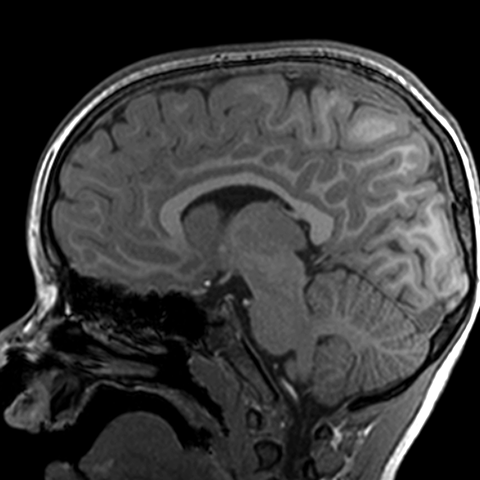

Sagittal view of cerebral hemispheres, MR [9 of 9]